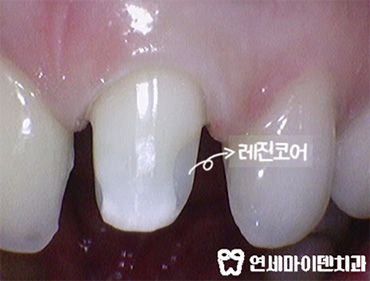

깨끗하게 내부 치료를 다시 하고 재감염이 없도록 레진코어까지 제대로 마무리했습니다.

앞니 재치료가 마무리 되었습니다.

앞니신경치료 후 치과 폐업으로 마음 고생이 심하셨는데

잘 마무리 되어서 좋아하셨어요 👍

보시는 것처럼 크라운도 예쁘게 마무리 되었습니다.

새로 한 크라운처럼 보이시나요?

원래 내 치아였던 것처럼 자연스러운 색상과 크기, 잇몸라인까지 잘 맞춰드렸습니다.

연세마이덴치과는 앞니 치료 시 <자연스럽게, 내 치아처럼, 대칭에 맞게> 를 가장 중요하게 생각합니다.

앞니신경치료 후 치아건강은 물론 심미성까지 모두 잡았습니다 ^^